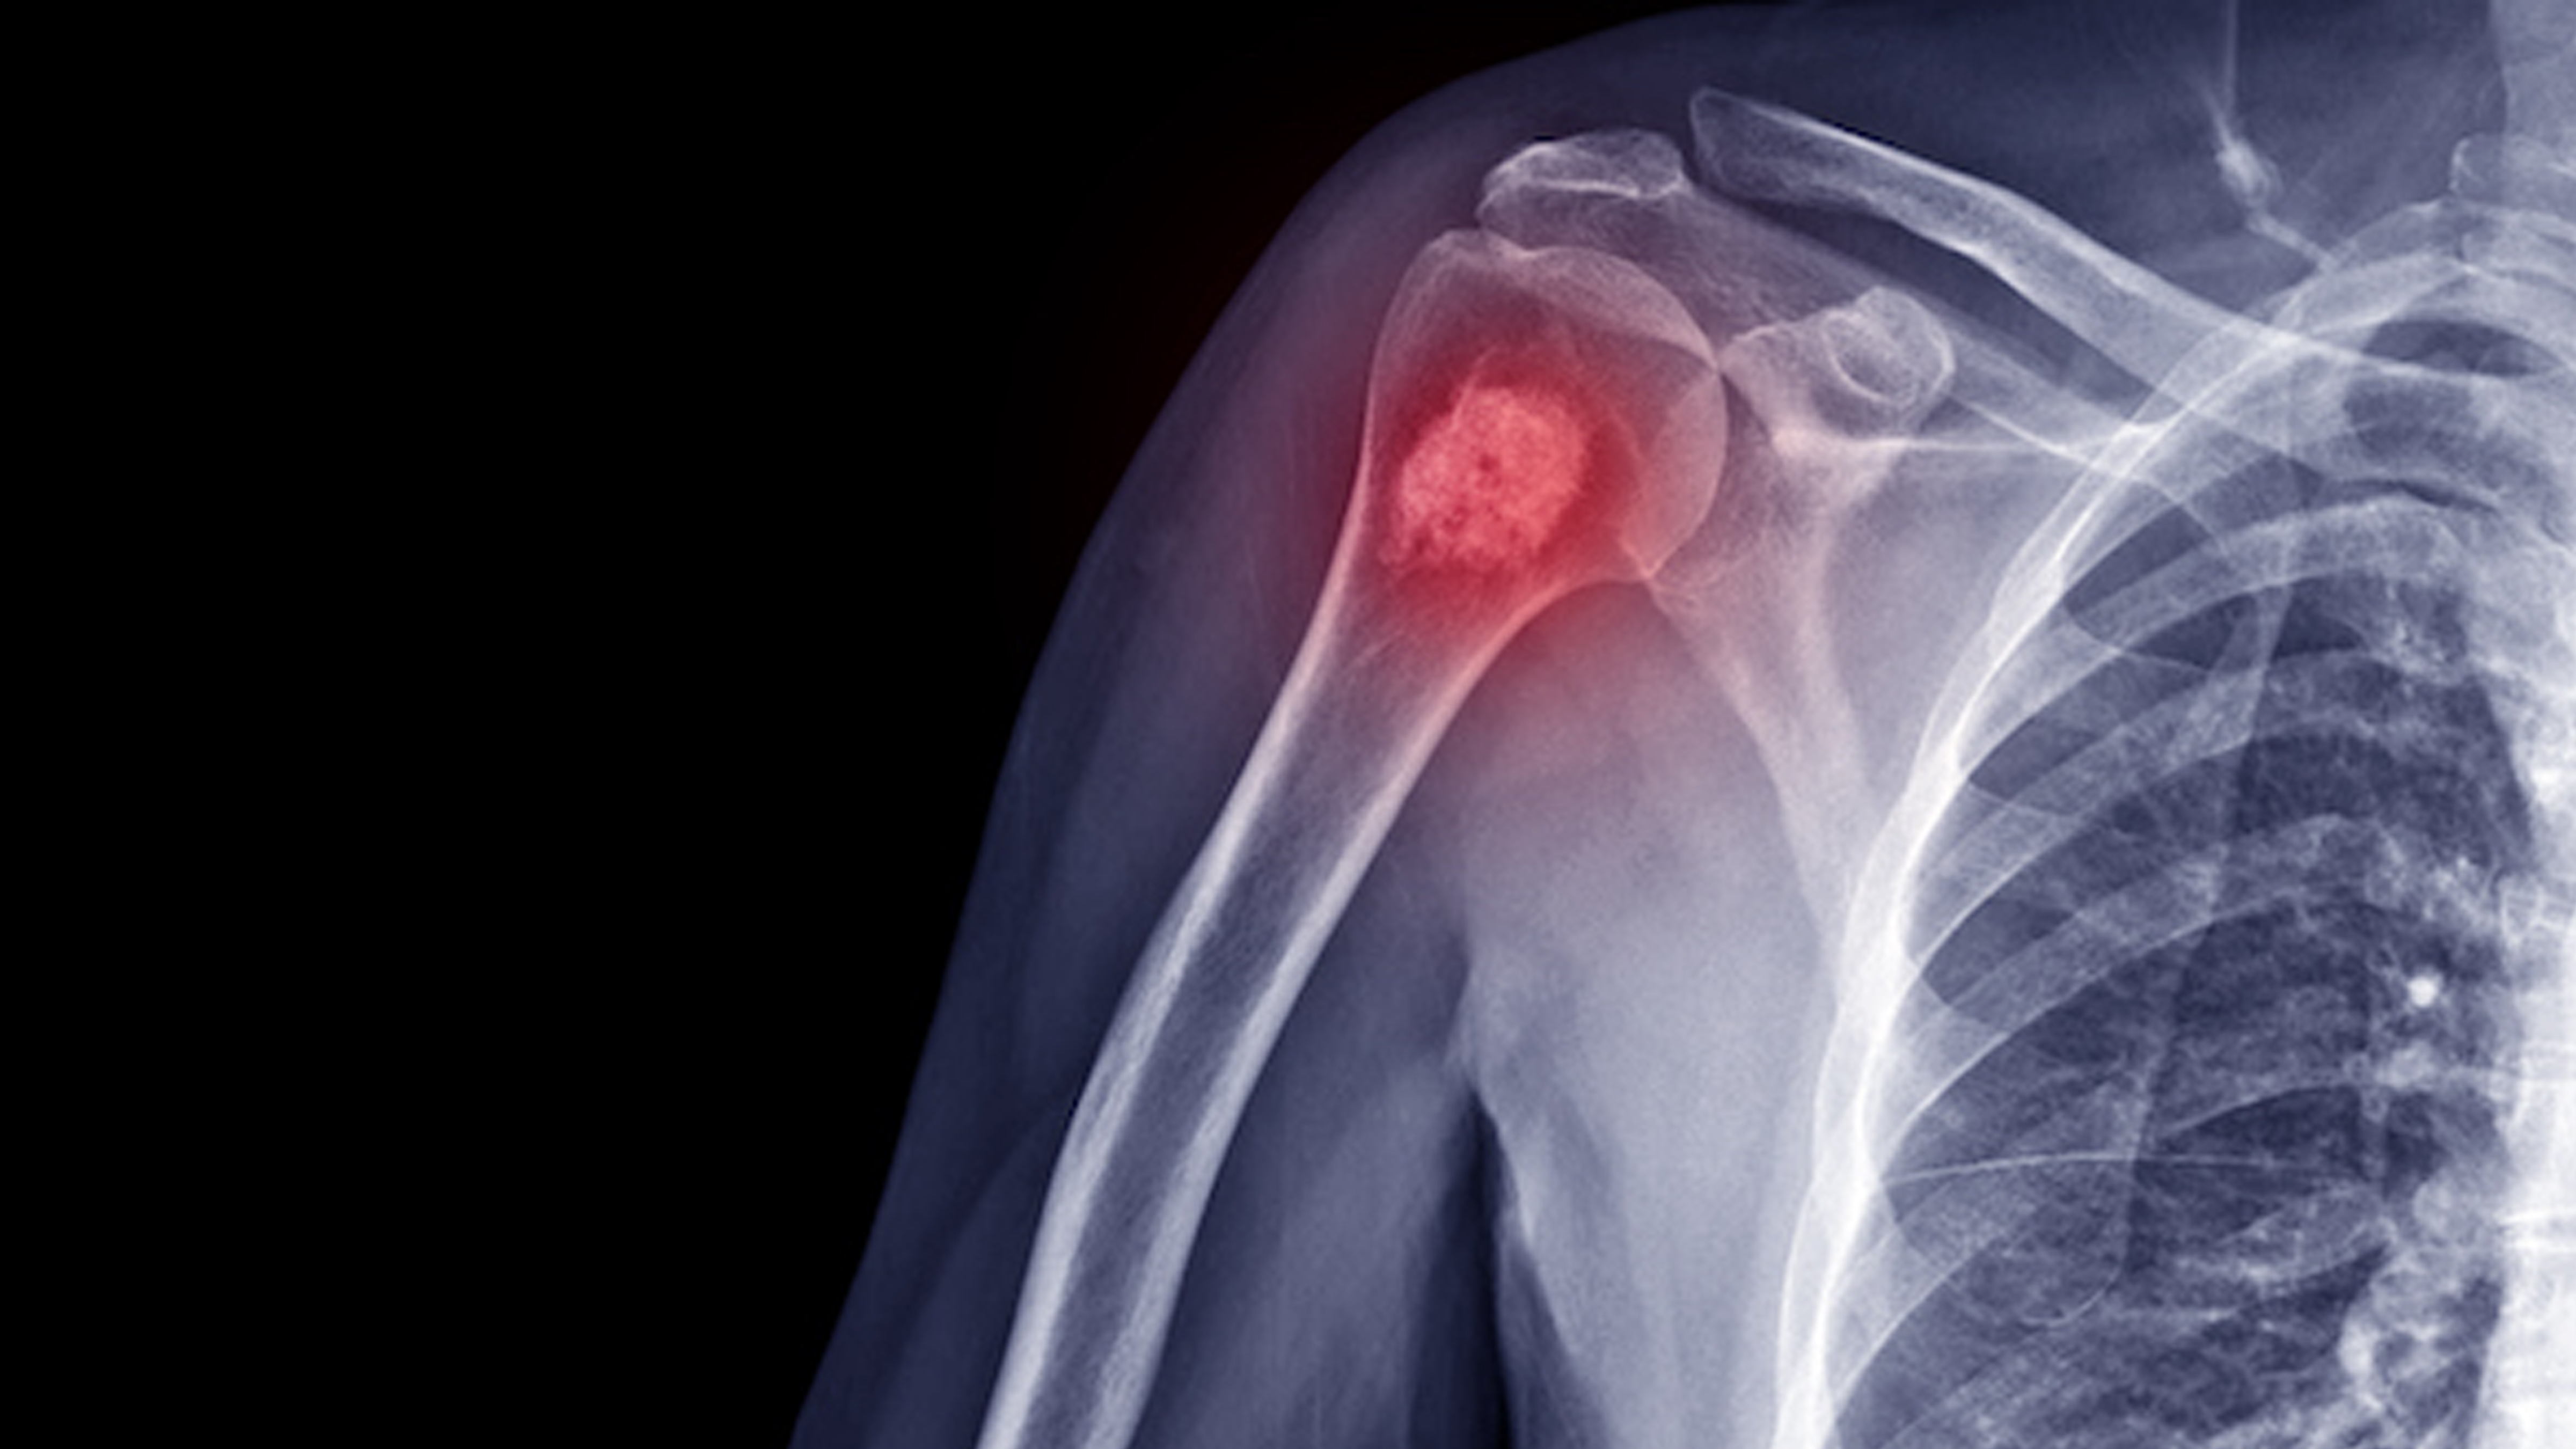

Expert Care for Bone & Soft Tissue Tumors

Orthopedic Oncology is a specialized field of orthopedic surgery focused on the diagnosis and treatment of bone and soft tissue tumors. At Subhash Ortho Clinic, Dubai, under the expert care of Dr. Subhash Ushakoyala, we provide comprehensive care for patients with benign and malignant musculoskeletal tumors.

Bone and soft tissue tumors can be benign (non-cancerous) or malignant (cancerous). Early diagnosis and treatment are essential for preserving limb function, preventing spread, and improving quality of life. We offer both surgical and non-surgical treatments tailored to each case.